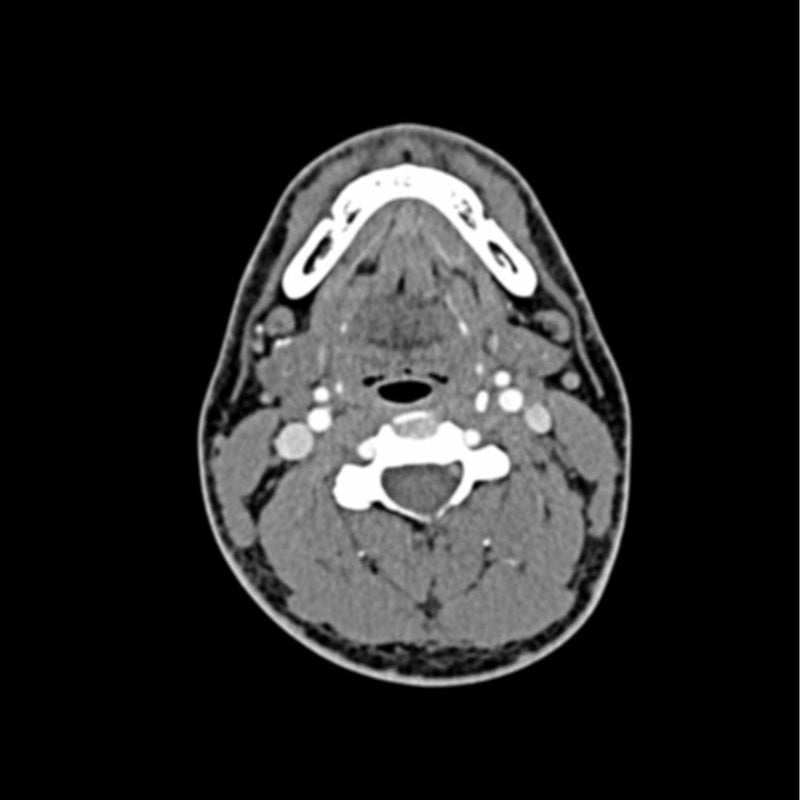

Head and Neck CTA Phantom AVM for CT Scan and X-Ray Training,

Head and Neck CTA Phantom AVM for CT Scan and X-Ray Training, CT Neck Scans - My Facial Pain,

CT Neck Scans - My Facial Pain, Contrast-enhanced computed tomography (CT) of the neck,

Contrast-enhanced computed tomography (CT) of the neck, Ultrahigh-Resolution Photon-Counting Detector CTA of the,

Ultrahigh-Resolution Photon-Counting Detector CTA of the, Ultrahigh-Resolution Photon-Counting Detector CTA of theご覧いただきありがとうございます。OMMOのNECK GATHER BALLOON CTネックギャザーバルーンコートです。色はモカ、サイズは36です。数回着用しました。2023awの完売商品です。軽くて温かいので、これから大活躍してくれると思います!素人の自宅保管品で完璧ではありませんので、ご理解いただける方にお願いいたします!バルーン型がとても可愛いです。